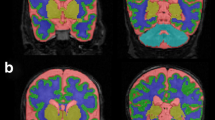

Preterm infants born ≤30 weeks’ gestation who did (n = 25) and did not (n = 59) have surgery requiring general anesthesia during the preterm period were studied. At TEA, infants had MRI scans performed with measures of brain tissue volumes, cortical surface area, Gyrification Index, and white matter microstructure. Neurodevelopmental follow-up with the Bayley Scales of Infant and Toddler Development, Third Edition was undertaken at 2 years of corrected age. Multivariate models, adjusted for clinical and social risk factors, were used to compare the groups.